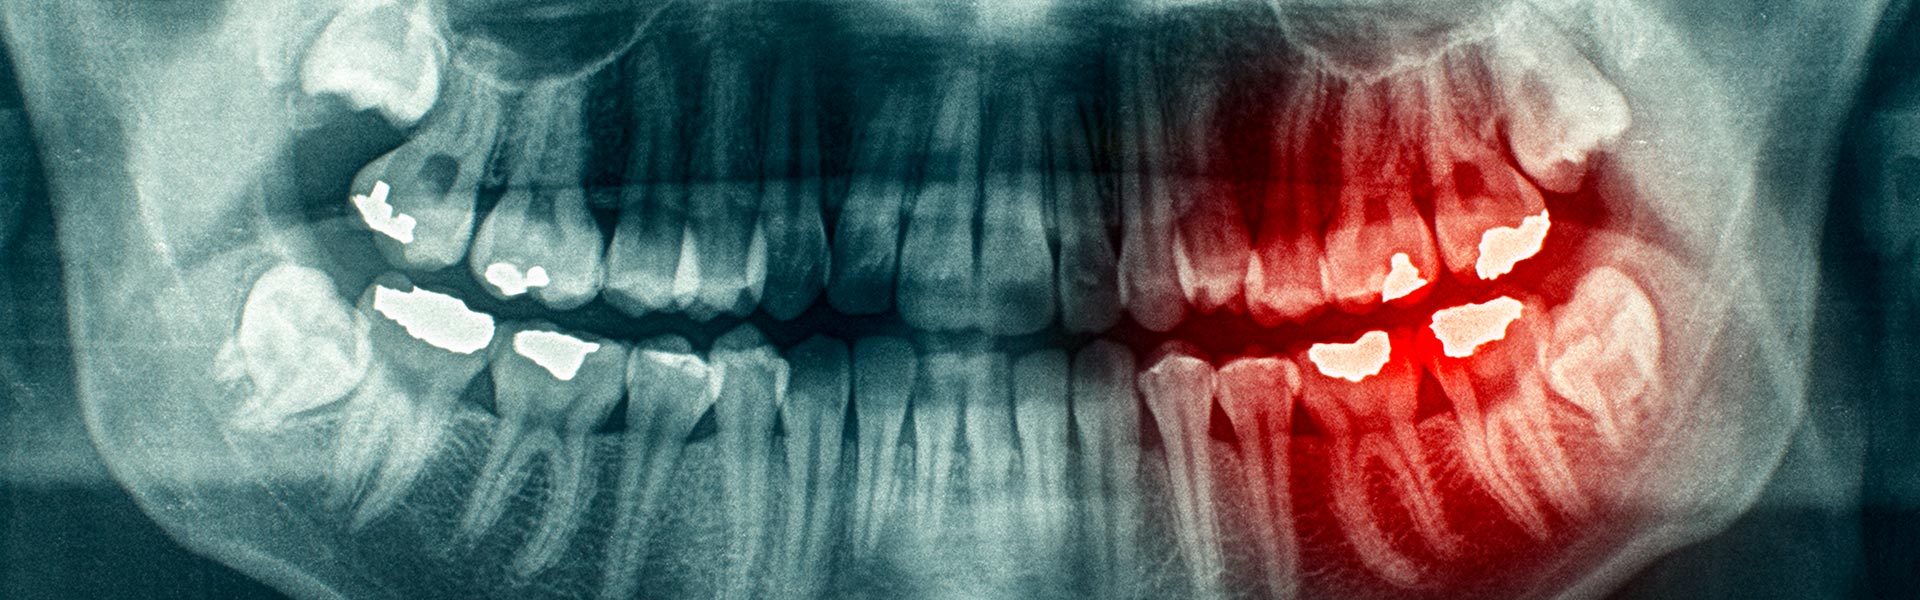

While adult teeth are meant to last a lifetime, there are times when wisdom teeth may need to be removed for the sake of your overall oral health. If you are experiencing any pain, discomfort or other issues related to your wisdom teeth, Neighbourhood Dental is here to offer a safe, efficient and gentle wisdom tooth removal!